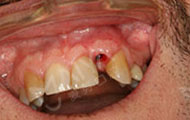

2016年4月 牙槽骨严重缺损,不适合一期种牙

来到深圳,多方寻医,一个医生朋友告诉我,这个只有到麦芽找郑苍尚院长,他能做。“我有6个月一直没有牙齿,我要我的牙齿。”这是我见到郑院长后说的第一句话,在麦芽流程很顺利,经过拍片检查后,郑院长说我剩余残根反复发炎松动,牙槽骨受损严重,影响咀嚼功能,只能拔除残根后需引导骨组织再生,不能一期种牙....很专业的词我不太懂,但是他能处理我就放心了!